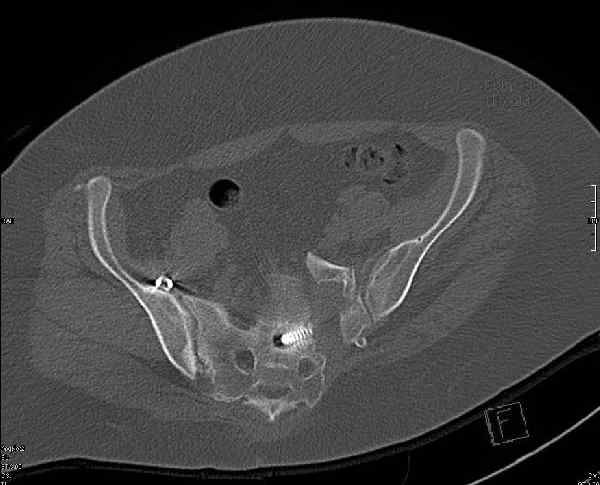

Могу сказать одно: миграция винтов и нестабильность синтеза левого подвздошно-крестцовогоо сочленения очевидна.

Мы имели ввиду перелом крестца

были использованы винты 7.2 мм, кроме того иетодика транссакральной фиксации не является общепринятой и широко рекомендуемой, но и в этих случаях они наблюдали случаи вторичного смещения

Забыл добавить, что ИХМО показан реостеосинтез более длинными винтами, с более широкой резьбой, с фиксацией за правое подвдошно-крестцовое сочленение.

Ув.коллега.Думаю, что реостеосинтез винтами бесперспективен.Пороз, наличие большого массива рубцовой ткани, невозможность создать жёсткую фиксацию в зоне ложного сустава крестца требуют изменеия вида остеосинтеза. Тут возможны два варианта.1) Открытый остеосинтез с атупластикой и фиксацией ВЧКО задним стержневым крестцовым аппаратом.2)Тоже самое, но фиксация 2 резьбовыми штифтами типа Штейнемана за заднюю ость подвздошной кости. От выдавливания крестца кпереди следует на этих гвоздяж зафиксировать реконструкционную пластину, которая винтами синтезирует фрагменты крестца.